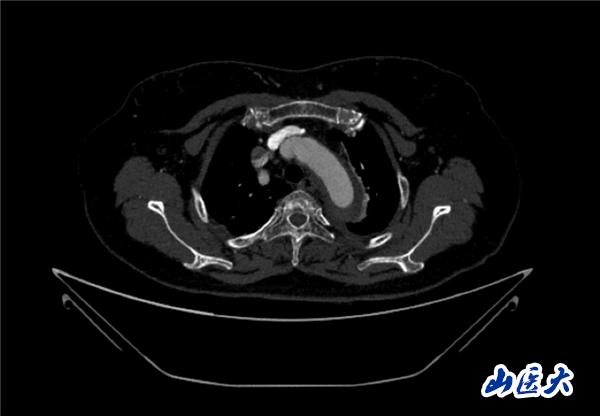

首例患者是一位55岁的女性,她患有高血压约2年时间,平时也会规律服用多种降压药,但血压控制始终不尽人意。2023年4月下午,她出现不明原因的头痛,在家拔罐缓解少许便未到医院就医,次日凌晨突感胸闷、胸背疼痛伴有呼吸困难等症状、家人急忙拨打了120,把患者送入医院急诊科进行救治,医生在急诊科行胸腹主动脉CTA时,显示主动脉弓部-降主动脉及腹主动脉壁间血肿,遂收治入医院血管外科,患者入院10天后复查血肿仍未有改善,依然伴有胸背部疼痛等不适,如不进一步处理,可能发展为夹层危及生命,患者及家属经过与医生团队了解沟通,决定进行创伤小、恢复快的介入手术治疗。张玮教授、符伟国教授、董红霖教授及其血管外科团队(闫盛、常文凯、田琴琴)共同商讨手术方案,最终确定使用Zipper™一体式主动脉弓覆膜支架系统,行胸主动脉覆膜支架腔内隔绝术+无名动脉、左颈总动脉、左锁骨下动脉分支重建术为患者进行治疗。董红霖教授及其血管外科团队根据患者术前头颅CT平扫提示双侧侧脑室旁缺血灶,血压控制不稳定,属夹层壁间血肿非典型夹层等风险点,制定了完整的手术方案,术中经股动脉置入Zipper支架主体,经预留导丝超选无名动脉,并确保主体支架对位准确,顺利置入左颈总动脉、左锁骨下动脉支架,重建弓上三分支。手术过程非常顺利。术后观察主动脉及分支覆膜支架定位准确;无内漏;分支支架通畅,动脉供血正常。

术后效果